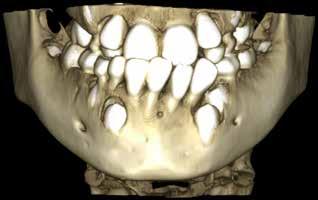

Patienttilfælde 1 (Fig. 1) er en 37-årig kvinde, henvist efter succesfuld behandling af stadie 3-parodontitis. Der er nu sundt

Før behandling

parodontium, ingen pocher over 4 mm, og både blødnings- og plakindeks er under 10 %. Patienten er motiveret for ortodontisk behandling, da hendes tænder er vandret over tid, delvist som følge af reduceret parodontium.

Der ses anterior trangstilling i begge kæber og overerupterede 1+1 og 2,1-1,2, hvilket resulterer i dybt bid med 2- tæt på ganepåbidning. Der er normale sidetandsrelationer, men der ses 5 mm horisontalt overbid (HOB) og 7 mm vertikalt

overbid (VOB). Papillen mellem 1+1 er betydeligt reduceret pga. fæstetab, og de mesialt kippede 1+1 har resulteret i en ”dark triangle”. Den facioorale funktion er for nuværende i.a. Panoramarøntgen (Fig. 1, I) viser marginalt knogletab i begge kæber og fravær af 8,7+7,8 og 8,7-8.